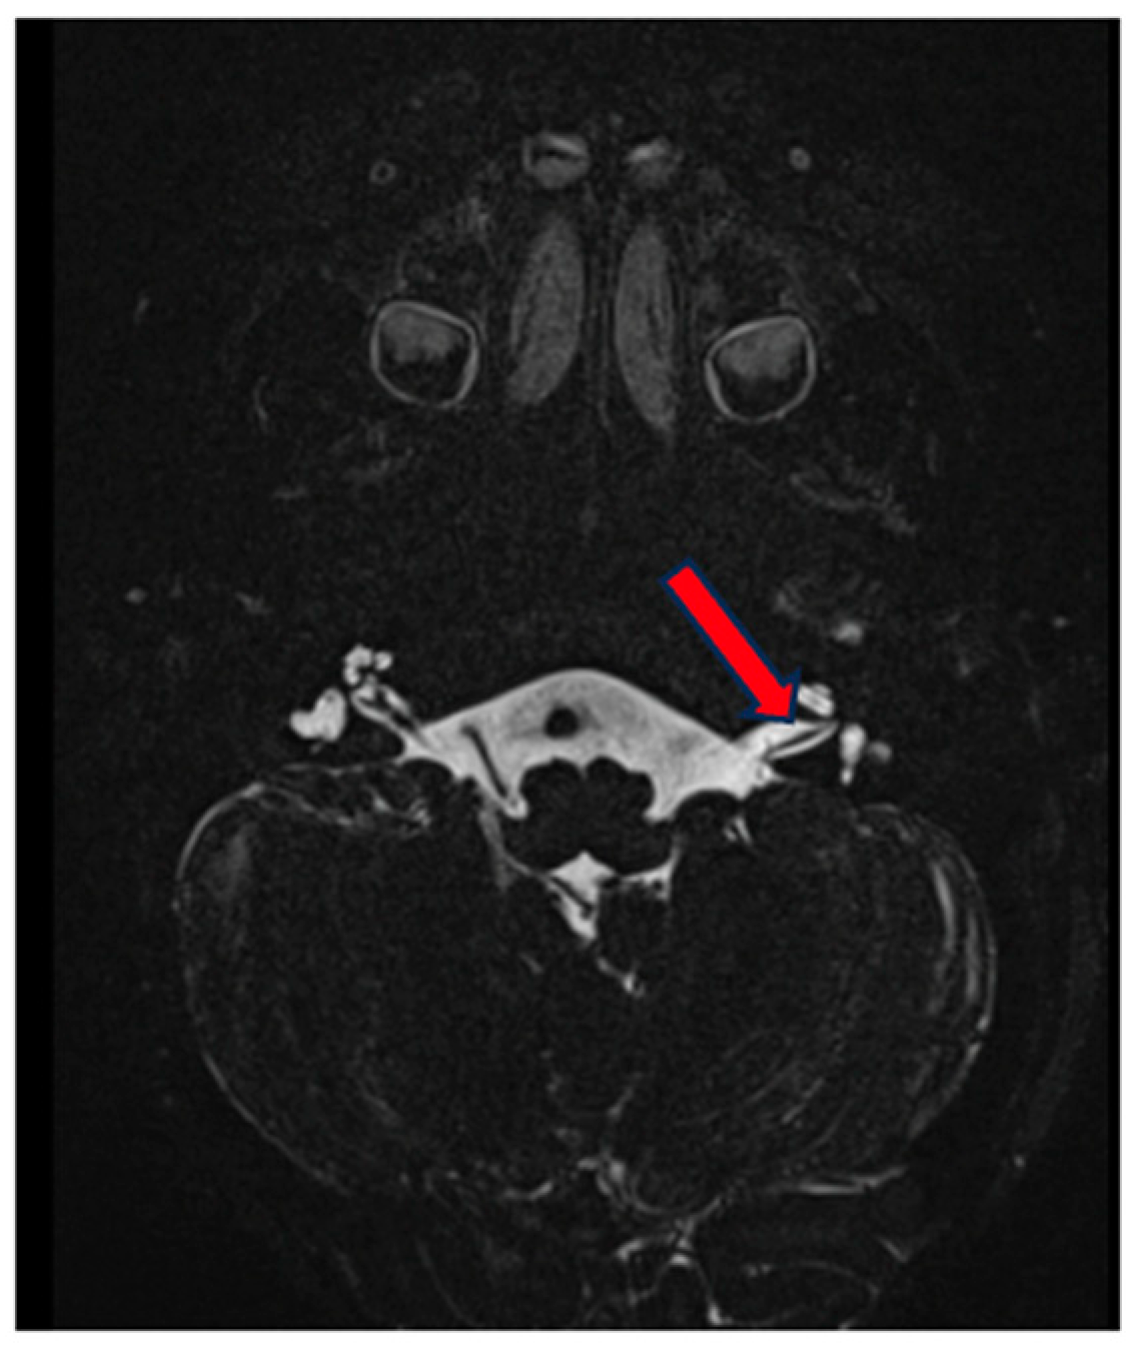

MRI correlated to the findings of the vestibular exam, revealing a normal fluid signal in the cochlea and vestibulum, as well as in the upper semicircular canal. Aberrant morphology with a blunt appearance of the lateral semicircular canal, which lacks a central opening, and partly also of the posterior semicircular canal, which appears smaller, with abnormal morphology and loss of the circular aspect. No widening of the vestibular aqueduct (Figure 4). There is a suspicion of hypoplasia of the left cochlear nerve, whereas the cochlea appears normally developed (Figure 5).

Figure 5.

MRI of the inner ear for case 2, T2 tse3d weighted image, hypoplasia of the left cochlear nerve (red arrow).